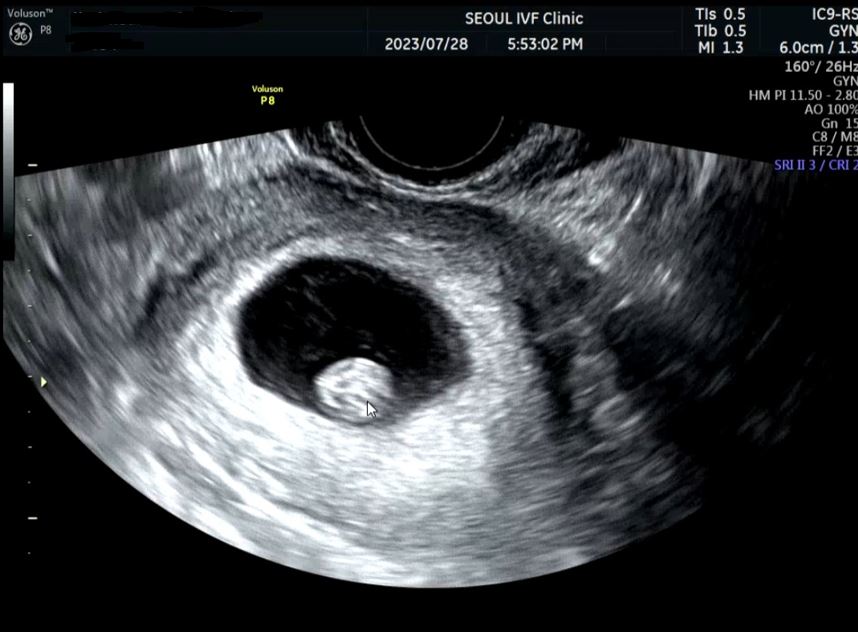

| 치료 도중 느꼈던 가장 기뻤던 순간과 절망적인 것들은 무엇인가요? 잊지 못할 경험이 있나요? | 정말 인공수정 준비를 위해 재검까지 하였는데 이번 배란일이 지난 3일~5일동안 밤에 오른쪽 와이존 느낌이 쎄 했어요~ 그 전에는 배 콕콕, 미식거림 임신 증상 느낌을 겪었던 저는 처음 느껴본 통증이였습니다. 그렇게 배란 9일차에 임테기에 손을 댔습니다. 세상 선명하게 두줄이 보였어요~ 그때 믿기지않아 이유정원장님과 약속 한 날짜까지 일주일 내내 임테기 확인을 했습니다. 그리고 피검을 통해 임신을 확인하였고 이주 뒤 초음파로 임신 확정을 받았어요~ 누구보다 응원해주신 이유정원장님! 원장님께서 기뻐해주시고 믿고 여기까지 와줘서 고맙다는 원장님 말씀은 평생 잊지 못할꺼 같아요😭❣ |